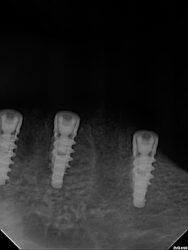

After un-covering buried implants for a mandibular overdenture, there was barely any keratinized tissue around the implants. 1mm at most. Instead of short locators, I’m thinking of getting the tissue around the implants better, are there techniques, materials, to do this non-invasively (meaning doing a complete re-flap)

• Typically many periodontists would say the gold standard is a FGG to help in those type of cases. Also, placing your implants deeper especially in thin biotype patients will greatly improve those cases as well.

• For vertical tissue growth, one successful technique i’ve been able to do especially in locator cases is using Alloderm. It will require a flap but essentially you release the flap like a GBR, use healing abutments to tack the alloderm along with sutures and close the flap. Don’t necessarily need air tight closure but I would definitely not…

Read more